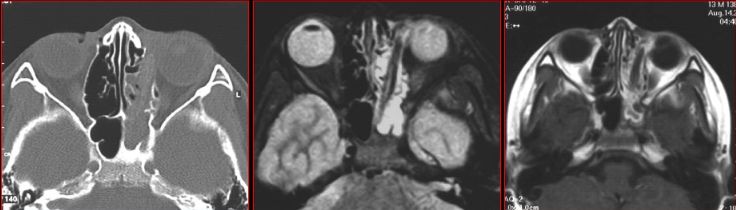

鼻窦霉菌感染

鼻窦爆发型霉菌感染